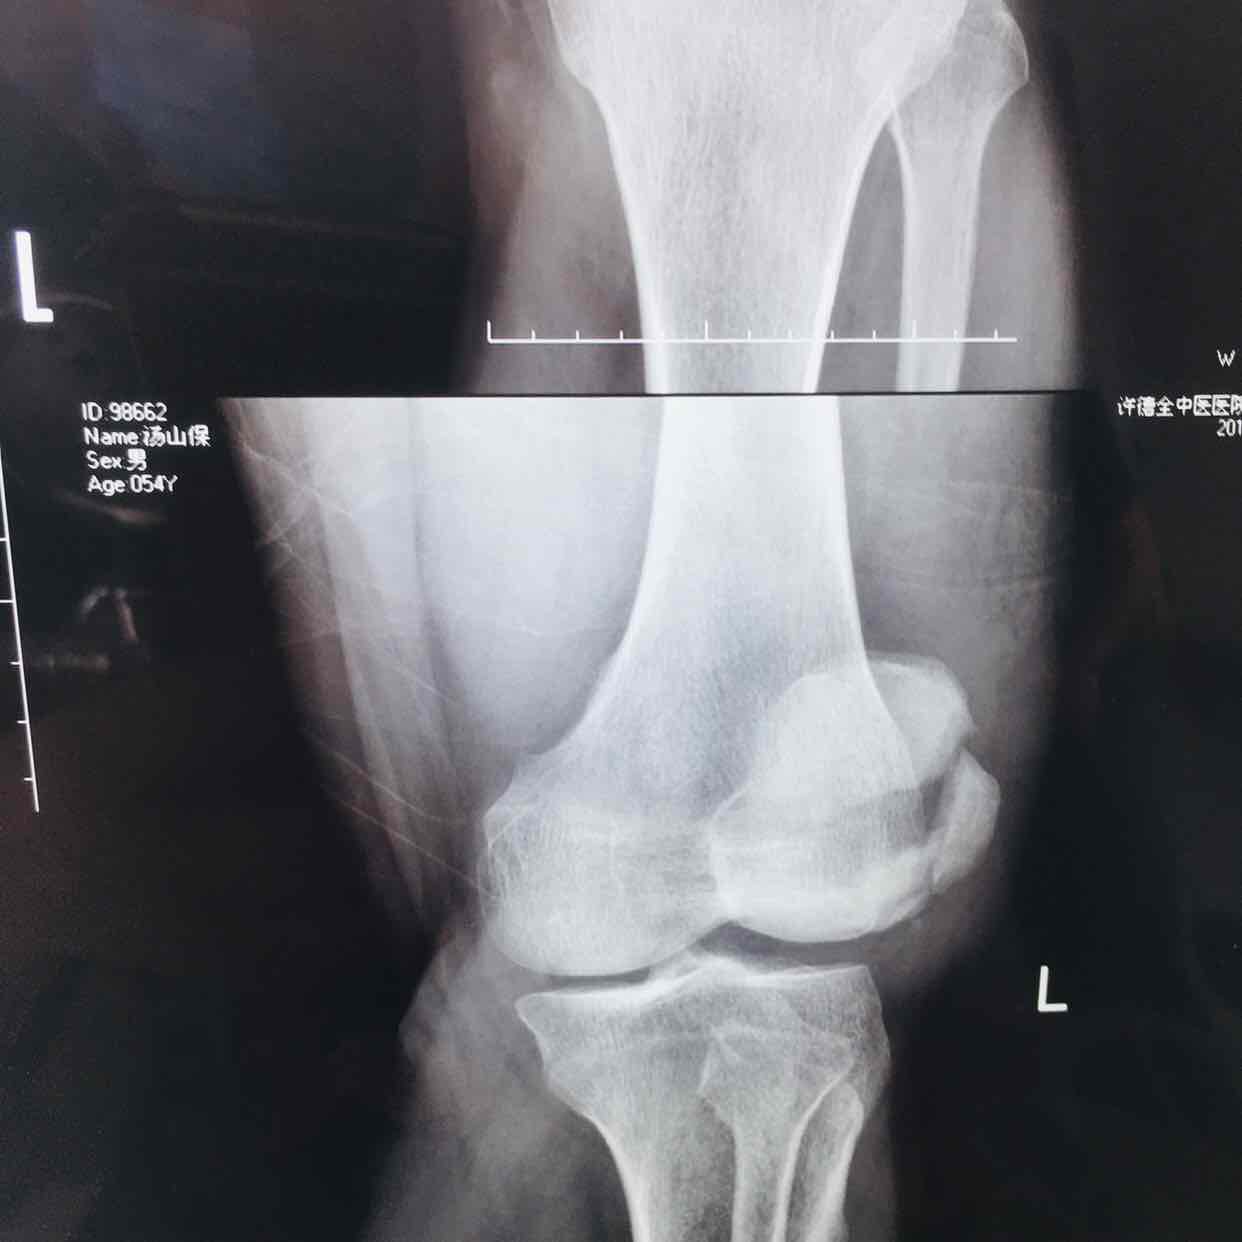

髌骨粉碎性骨折(髌骨爪➕克氏针固定)

摔伤后左膝部肿痛,活动受限1小时入院。既往身体健康,无特殊不良嗜好。

生命体征平稳,心肺复未见异常。左膝部肿胀明显,皮色发红,皮温高,压痛明显,可及骨折断端,伸膝关节受限,末梢血运感觉正常。

诊断左髌骨粉碎性骨折在腰麻下行切复内固定术,术后抗炎,消肿止痛等处理。